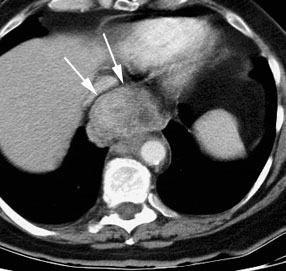

Chest ct scan showing invasion of the trachea by esophageal cancer.